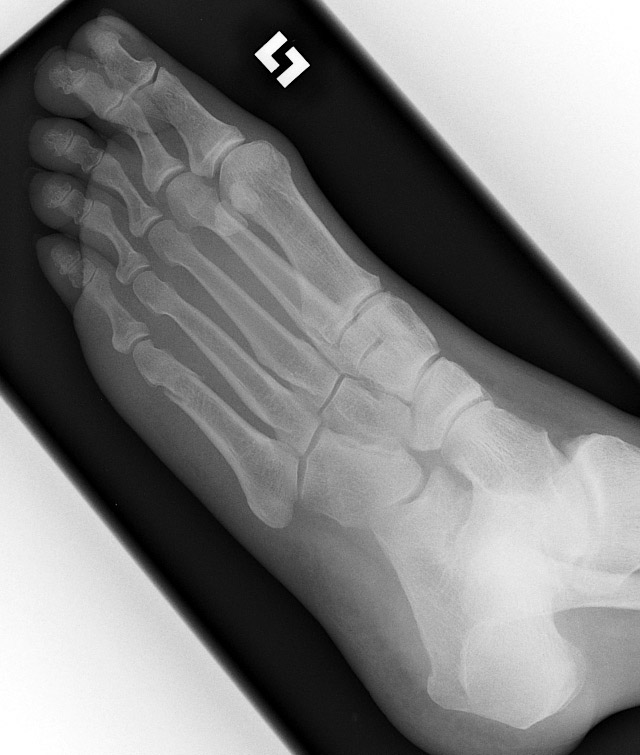

Return to Metatarsal Fracture